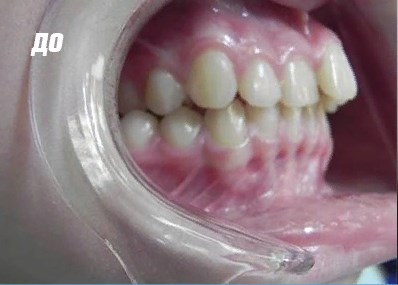

Пластинка для зубов: фото До и После

Нарушения прикуса возникают при выпадении молочных зубов и неправильном росте постоянных единиц. Чем раньше будет диагностирована патология и приняты меры, тем лучше пластинка справится со своим назначением.

Как действует пластинка

Для детских зубов важно направить на корни правильную нагрузку. Пластины помогут изменить ее направление, если формирование зубных рядов происходит неправильно. Выполняются слепки небной зоны и изготавливается пластиковая часть, возле которой удерживаются с помощью микроскопических замочков стальная или из титановых сплавов дуга. Направление смещения тщательно рассчитано. Молочные зубы ребенка имеют упрощенную корневую систему, поэтому важно рассчитать нагрузку точно, чтобы наоборот, не нанести вреда новым постоянным зубам, которые уже формируются под молочными.

Давление в ортодонтической пластине оказывается только в нужных местах, и не задействуется там, где небезопасно. Пластинка изготавливается несколько недель, а ношение ее растягивается на долгие месяцы. Но зато результат порадует - зубы выровняются, улыбка станет более эстетичной, а жевание – более практичным.